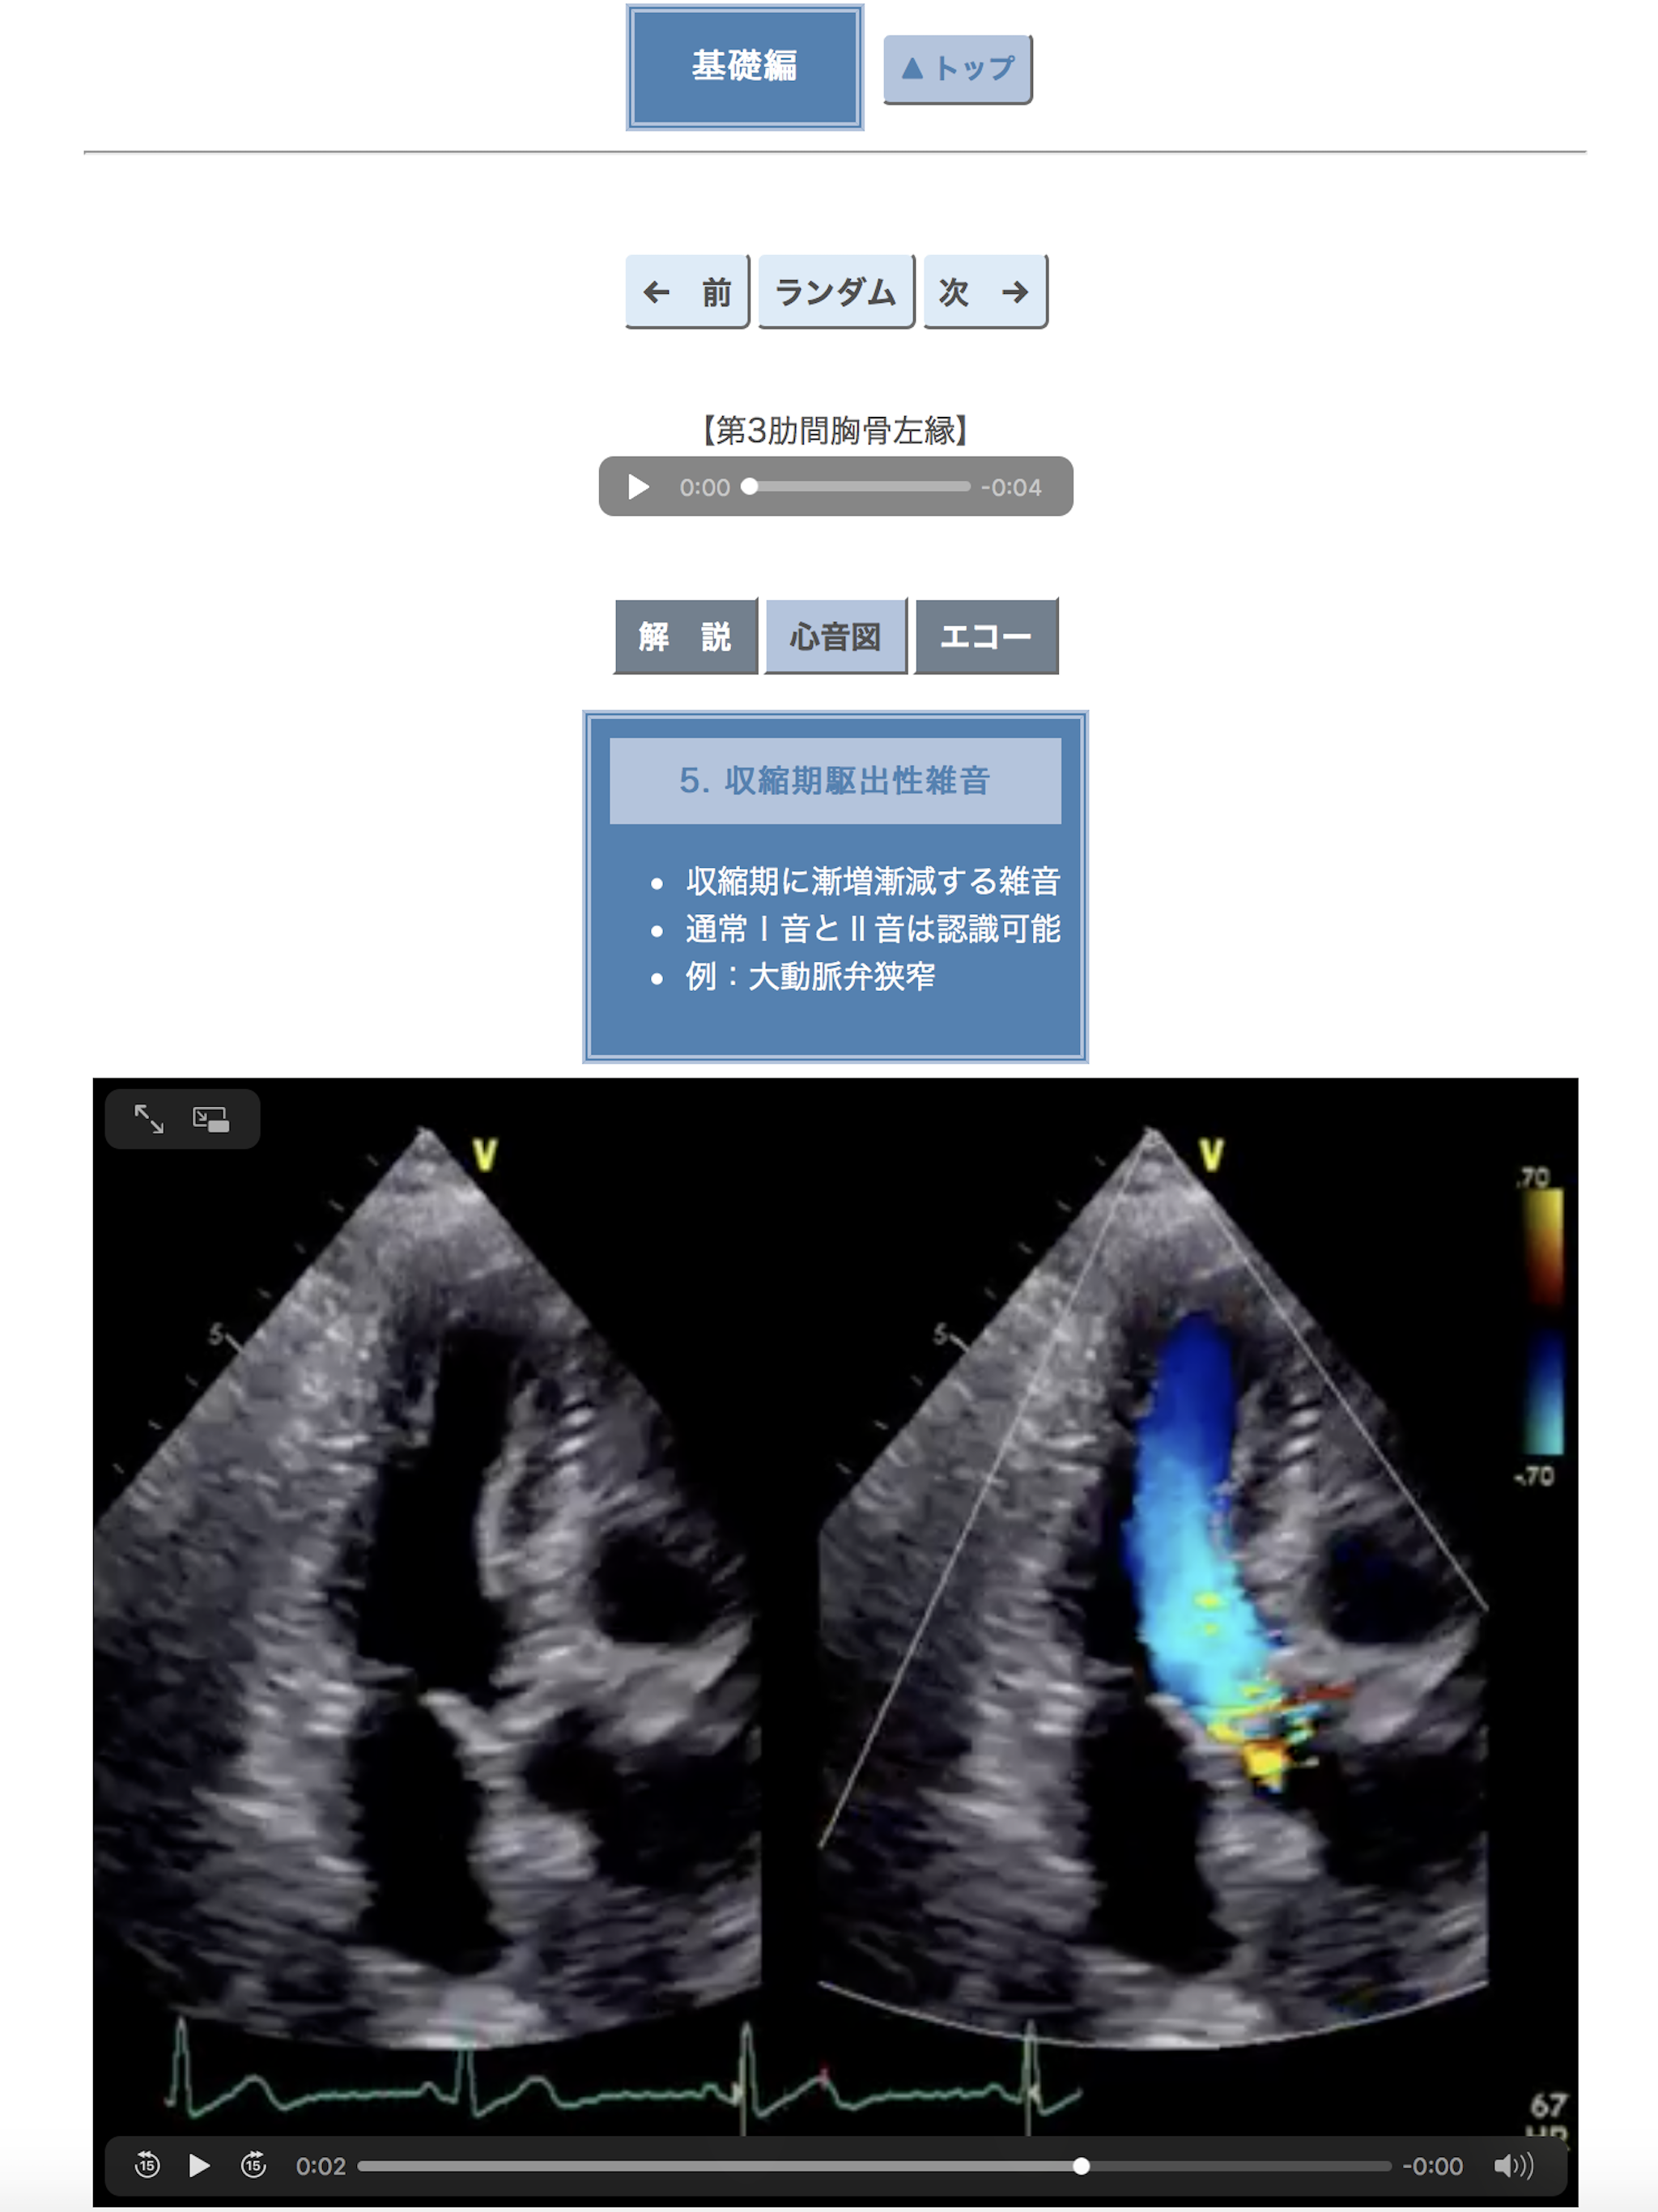

心臓はおしゃべりです.喜び,憂い,興奮,冷静,快さ,喘ぎ,充実,不満・・・いつも1人で何かを呟いています.うまく聞き取れないことも少なくありませんが,聴診器を胸に当てる前はいつも気持ちが高ぶります. この心臓語が持つ面白さを伝えるために本アプリ「ポケット心音」を作成しました.聴診器の歴史や心音のトリビアも紹介しています.心臓の聴診に興味を持つきっかけになればこれ以上の喜びはありません.